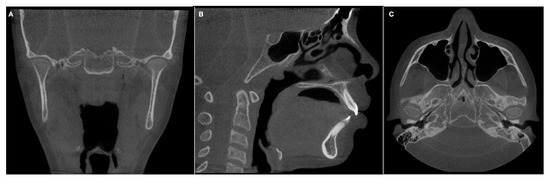

| Condylar axis | Inner angle between sagittal middle plane (SMP) and the line drawn from a projection of the highest middle-lateral length of each mandibular condyle. Figure 4. |